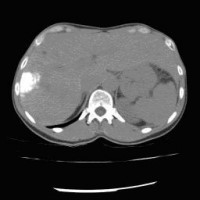

Computertomographische Darstellung eines hepatozellulären Karzinoms (Pfeil)

(Bild 1 von 5)

Computertomographische Dokumentation der Embolisateinlagerung innerhalb des Tumors nach transarterieller Chemoembolisation (TACE)

(Bild 2 von 5)